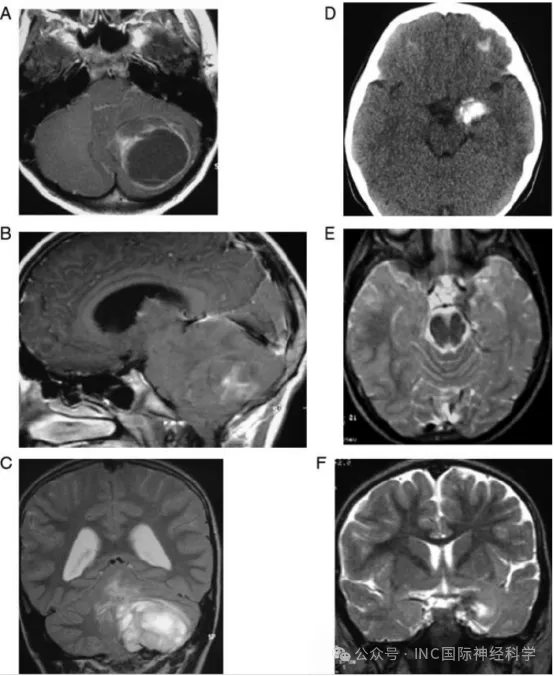

上面是两组不同肿瘤体积/占位效应与神经认知状态之间的对比。左侧列(A-C)的患儿为左侧小脑半球巨大毛细胞型星形细胞瘤(WHO I级),巨大的囊性肿瘤明显压迫到了小脑及脑干,幕下高压又进一步导致继发枕骨大孔扁桃体下疝,同时伴有脑积水。然而,尽管存在如此显著的占位、扁桃体下疝及脑积水,该患儿的认知功能却是正常的。

那么右侧列(D-F)的患儿呢?可以明显看出,肿瘤的体积小了不止一圈,同样为低级别的神经节细胞胶质瘤,与左侧那位患儿相比,右侧的患儿病情似乎减轻不少,病灶广泛钙化,无水肿,肿瘤局限于颞叶钩回,占位效应轻微。奇怪的是,尽管病灶小、局灶效应极轻,但患儿却表现为重度精神发育迟缓及自闭症。